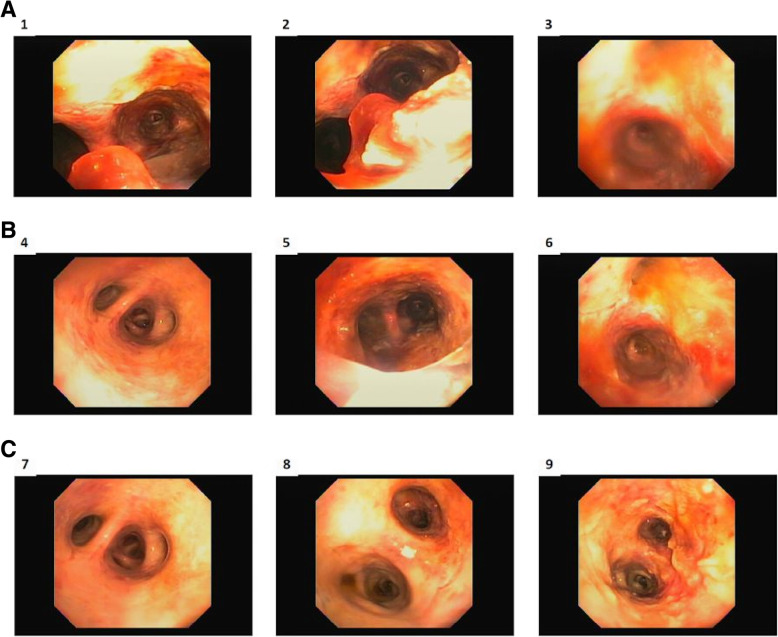

His respiratory status declined rapidly, and he was transferred to the intensive care unit (ICU) and intubated for respiratory failure. The patient underwent a bronchoscopy which revealed copious airway secretions and a thick, sloughing, erythematous mucosa. Bronchoalveolar lavage (BAL) yielded degenerated material with benign pulmonary elements and acute inflammation, but no signs of malignancy. The bronchoscopy revealed severely denuded airways throughout the lungs consistent with an inhalational injury likely due to vaping (see bronchoscopic images, Fig. 2).

He had no clinical history of inhalational injury other than the vaping exposure. He had severe progressive refractory respiratory failure despite maximal ventilatory strategies with a progressive increase in airway pressure and dropping Pa02/Fi02 ratio. At this time, he became hypotensive and was vasopressor dependent. Treatment was started with vitamin C, thiamine, hydrocortisone and multiple antibiotics (vancomycin, cefepime, azithromycin and doxycycline) for concern of sepsis as well as oseltamivir for Influenza A. Despite antibiotic treatment, his hypoxic respiratory failure further progressed and he required aggressive ventilatory support with a positive end-expiratory pressure (PEEP) of up to 30. The patient’s Pa02/Fi02 ratio was only 37 when the extracorporeal membrane oxygenation (ECMO) team was contacted and a bilateral femoral veno-venous (V-V) ECMO was placed at the spoke institution as part of our mobile ECMO program and patient was brought to our hub institution. After the procedure he was stable enough to be transferred to our facility. Despite the V-V ECMO, the patient required multiple vasopressors and although his lactic acid decreased initially, there was a progressive need for escalatory support and patient was converted patient from V-V ECMO to veno-arterial (V-A) ECMO. Given severe sepsis with shock, the peripheral V-A ECMO was deemed to be insufficient to provide hemodynamic support, and he was subsequently placed on central V-A ECMO to improve end-organ function. The patient’s clinical course was complicated by acute kidney failure for which he required dialysis, liver failure and encephalopathy which was likely secondary to his metabolic derailment and sepsis. He also experienced multiple episodes of atrial fibrillation with rapid ventricular response for which he was successfully cardioverted three times. A transthoracic echocardiogram showed a severely dilated right ventricle as well as biventricular systolic dysfunction. Due to a worsening pulmonary edema, he was emergently placed on an intra-aortic balloon pump (IABP). Although the CXR showed subsequent improvement in aeration with improvement in minute ventilation on the ventilator (Fig. 3), the patient also developed severe limb ischemia with skin mottling and ecchymoses on his extremities, trunk, nose and ears. Sepsis and cytokine storm with severe vasoplegia requiring vasopressors were determined to the ongoing issue. Severely diminished tibial flow and thrombi in the bilateral posterior tibial arteries was seen on vascular ultrasound and out of concern for compartment syndrome the patient underwent a fasciotomy. During this time, patient was awake, alert and communicative with the family at the bedside. Despite our best efforts, non-viable muscle was seen in all four compartments bilaterally and a bilateral through-knee amputation was performed. Confronted with the patient’s poor prognosis, the family decided to suspend life-supporting measures in favor of transition to comfort care. The patient expired shortly after the IABP and ECMO were turned off. In total, the patient spent two weeks in the hospital. The family consented to an autopsy.

The critical questions in this case are how and why a young man would die after such a short clinical course which began as an upper respiratory infection. The patient had lymphopenia suggesting he was immunocompromised. Why? By reviewing the patient’s history, we propose that the patient’s vaping with inhalation of a Vitamin E acetate and tetrahydrocannabinol mixture had a major role. In our case, the Oil Red O stain, which stains the lipid droplets in macrophages/ histiocytes, was strongly positive in the sections from the patient’s lungs. This is supporting evidence of vaping, but it is not specific [ref. 9–ref. 11]. However, acute inhalational injury was documented by video bronchoscopy, and this provided confirmatory evidence of the vaping-induced lung injury [ref. 3–ref. 7, ref. 12, ref. 13].

Bronchoscopy in our patient showed severely denuded airways as seen in inhalational injury—a finding that has not been previously reported with vaping-related illnesses. Additionally, vaping likely triggered the respiratory failure in this influenza patient—another new finding. Other striking findings under microscopic examination were the relatively diffuse epicardial lymphoplasmacytic infiltrate and patchy interstitial lymphoplasmacytic infiltrate in both kidneys, likely related to viral infection.